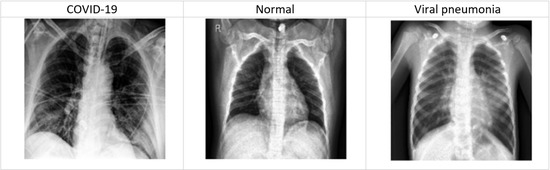

3.2. Detecting COVID-19 Based on the Dataset of Chest X-ray Images

3.2.1. COVID-19 Chest X-ray Images Description

- COVID-19 -chest-X-ray-1

- COVID-19-chest-X-ray-2